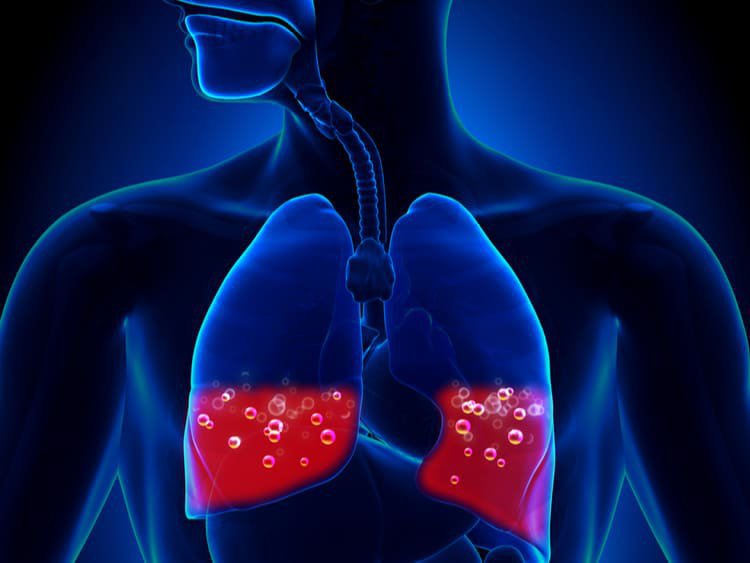

- Di chuyển của giá đỡ kim loại có thể gây thủng tâm nhĩ và gây phù phổi cấp. Đây là biến chứng hiếm gặp